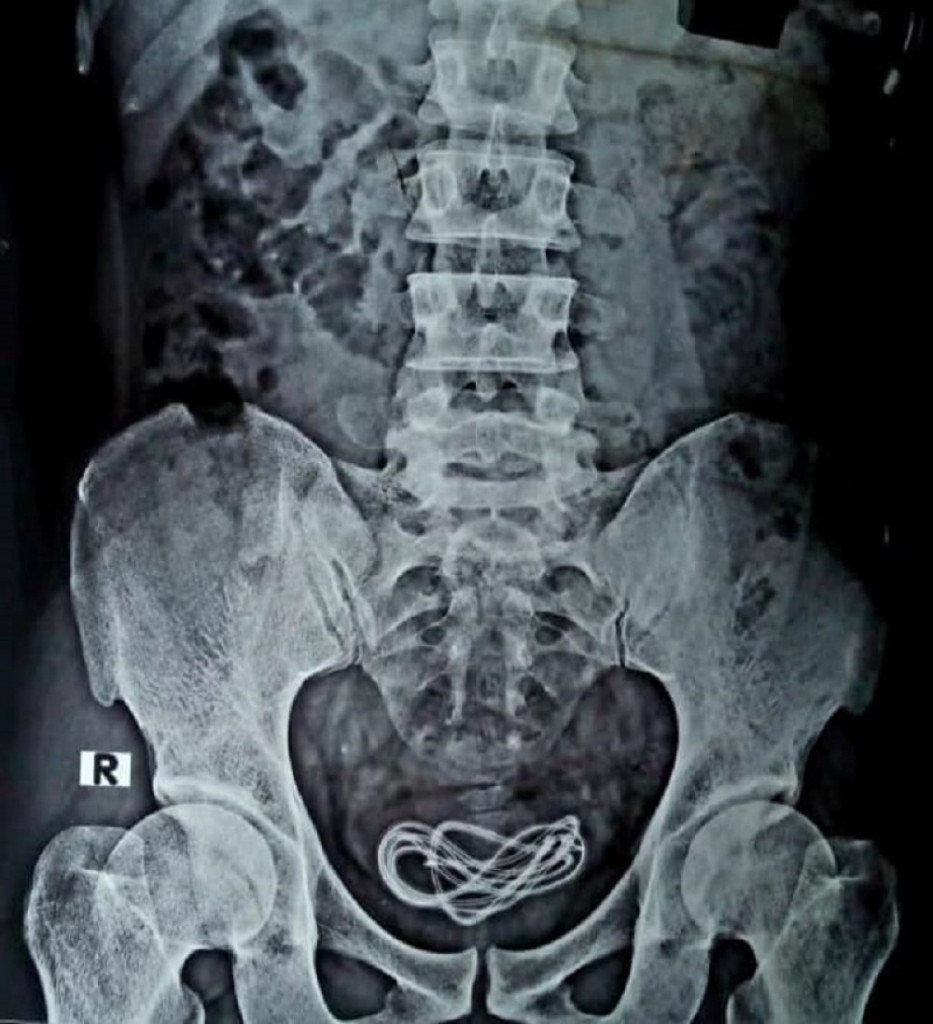

Izvešteno je da je Demkina koristila slike da bi prikazala lekare. Jednom od lekara pokazala je sliku nečega u njegovom stomaku. To je bio njegov čir.